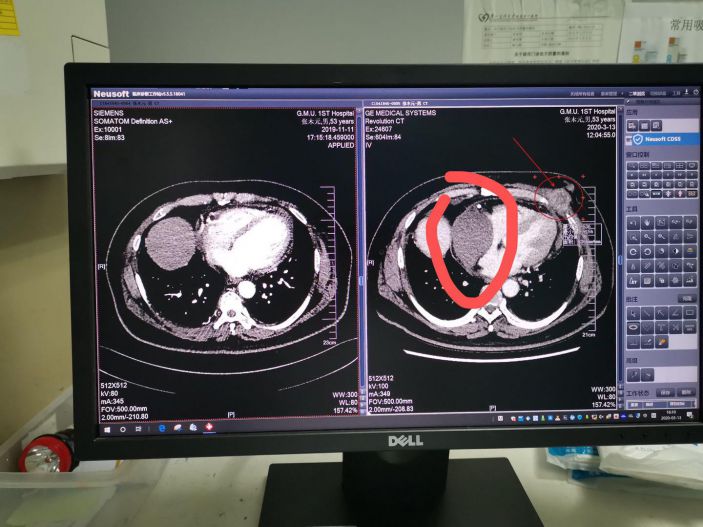

入院時,患者上腔靜脈及右心房右心室都被腫塊明顯擠壓,出現上腔靜脈綜合征,顔面浮腫端坐呼吸。入院後予下肢輸液,應用大劑量糖皮質激素及呋塞米治療後症狀稍減輕。

一開始患者家屬很不信任我們,但是有兩個巧合:第一個巧合是我去年去廣州參加一個介入會議回來的時候和患者同坐一個班次高鐵,一路上聊了很多,知道他是一個很豁達的人,也知道他在口服泰瑞莎之後我告訴他可以來我院辦理特殊門診,後來他也來辦理了特殊門診;第二個巧合是查房時,患者無意中說一個月前在我院門診複查過CT,我看了患者一個月前的CT片并沒有心包腫塊就感覺不對勁,因爲一個月内長這麽大的轉移瘤可能性很小。

于是我主動和患者在廣州的主管醫師溝通,他也覺得奇怪。爲了這個事,我先找我院影像科的胡主任看片,胡主任的意見是實性腫塊伴強化,考慮轉移可能性大,但是強化不是特别強,不能排除其它可能。我又找了超聲科陳主任做了一個心髒彩超,陳主任說超聲顯示是實性腫塊,但是腫塊回聲有不均勻,除了腫瘤以外有一個很小的可能是陳舊血腫,但是超聲下很難定位。患者在超聲科聽到我和陳主任的對話之後就說我現在生不如死,不能平卧,吃不下東西,他說李主任你放心去治,就算死了我也不怨你。我又請了胸外科張曉忠主任來會診,張主任也覺得一個月内長這麽大的轉移性腫瘤可能性不大,這進一步堅定我的判斷——這并非轉移瘤,而是心包内巨大血腫。

經CT定位,隻有一個間隙可以進針,我和外三科主任張曉忠一起上台穿刺,小心翼翼一針穿刺下去,出來的是黑色的血,證明我的判斷是正确的。引流出來後,患者的呼吸困難馬上就緩解了。術後患者終于能進食又能睡個安穩覺了。